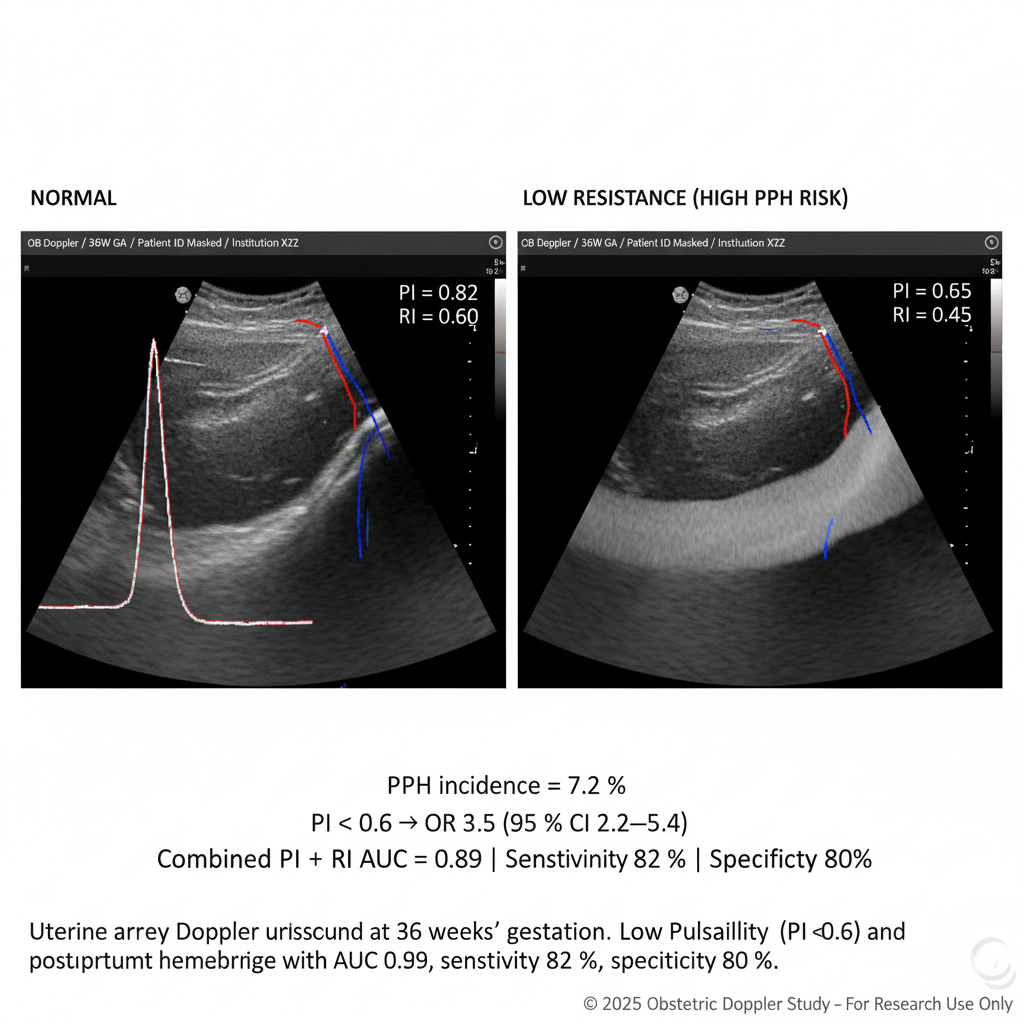

Methods: In a prospective cohort of 986 pregnant women enrolled from three tertiary obstetric centers between 2022 and 2024, uterine artery Doppler ultrasound was performed at 36 weeks to record pulsatility index (PI) and resistance index (RI). Clinical variables included parity, hemoglobin, labor duration, and prior obstetric history. Outcomes of postpartum hemorrhage (≥ 1000 mL blood loss within 24h) were recorded. Logistic regression and ROC analysis were used to build predictive models.

Results: The incidence of PPH in the cohort was 7.2 % (n = 71). Women who developed PPH had significantly lower mean uterine artery PI (0.57 ± 0.08) compared to non-PPH (0.65 ± 0.10), p < 0.001, and RI (0.78 ± 0.05 vs 0.84 ± 0.07, p < 0.001). A combined model incorporating PI, RI, parity ≥ 3, and labor duration > 12 hours achieved an AUC of 0.89 (95 % CI: 0.85–0.93), with sensitivity 82 %, specificity 80 %. In multivariable analysis, PI < 0.60 (OR = 3.5, 95 % CI 2.2–5.4), multiparity (OR = 2.1), and prolonged labor (OR = 1.8) remained independent predictors. Women in the top risk decile (predicted probability > 0.20) had a PPH incidence of 23 %, versus 3.4 % in the low-risk decile.

Conclusion: Uterine Doppler flow indices measured in late pregnancy significantly predict risk of postpartum hemorrhage. When combined with clinical parameters, the model reliably stratifies patients at high risk. Incorporation of Doppler screening into routine antenatal assessment could enable preemptive measures (uterotonics, blood planning, monitoring) to reduce maternal morbidity and mortality.